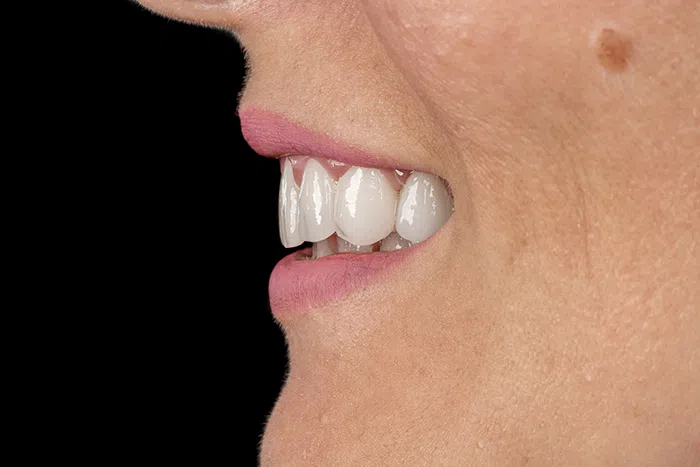

După

Caz de estetică dentară – Fațete ceramică presată E-Max

Provocarea acestui caz a fost în prepararea minim invazivă a dinților centrali rotați și a obține o formă și o culoare cât mai naturală, pacienta dorind un caz de estetică dentară ce să nu fie observabil.

Pacienta a beneficiat de corecție gingivala cu laser pentru uniformizarea asimetriilor gingivale, tratamente endodontice de canal sub microscop, obturațiile vechi (plombe) schimbate cu materiale de compozit cu particule nanoceramice, și fațete dentare din ceramică presată E-Max.

Termen de finalizare 2 săptămâni de la amprentarea finală.